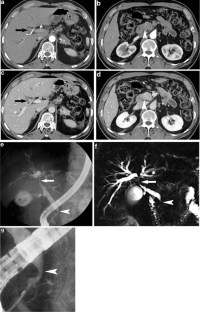

Fig. 2